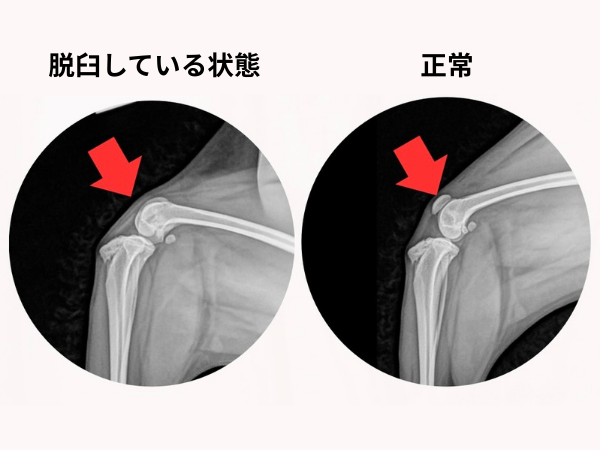

- 膝蓋骨脱臼

<術前のレントゲン>

膝蓋骨が内方に脱臼しています。